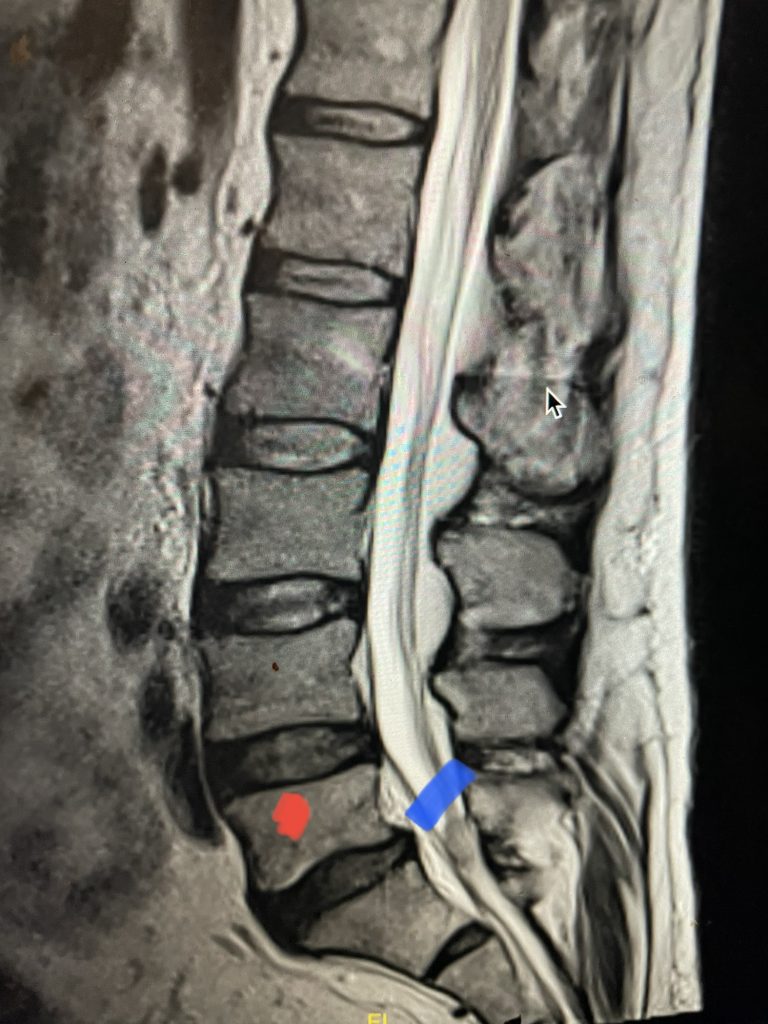

Another interesting 54-year-old patient presented with low back pain and severe left lower extremity pain over two months. He had a history of falls. The pain in the leg was more bothersome to the patient. The patient had a work-up with an MRI and CT of the lumbar spine. MRI demonstrated a subtle grade 1 spondylolisthesis L5-S1 with a dysmorphic L5 vertebral body (Fig 2). There was a suggestion of a left L5 spondylolysis or defect in the bridge of bone that connects the superior facet process of the segment and the inferior facet process. A CT of the lumbar confirmed this unilateral abnormality which certainly could account for the patient’s left leg pain (Fig 3). This is an unusual finding in that most patients have bilateral pars defects. Patients with L5-S1 often have congenital abnormalities of the lumbosacral junction including weird shaped, elongated or dysplastic facet joints. A subtle L5-S1 spondylolisthesis with an associated smaller and misshapen L5 vertebral body is often associated with L5 spondylolysis. In addition, with a dysmorphic L5 vertebral body, there is secondary disc degeneration at L5-S1 and sometimes at the L4-5 disc with an associated retrolisthesis at L4-5. There is less surface to surface contact of the L4-5 and L5-S1 leading to chronic segmental instability.

Fig 2: Sagittal T2-weighted MRI of the lumbar spine demonstrating a dysmorphic, trapezoidal-shaped L5 vertebral body (red dot) and a subtle grade 1 spondylolisthesis L5-S1 (blue line).